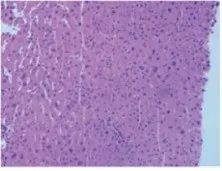

组织学观察是将病变组织制成厚约数微米的切片,经不同方法染色后用显微镜观察其细微病变,从而千百倍地提高了肉眼观察的分辨能力,加深了对疾病和病变的认识,是最常用的观察、研究疾病的手段之一。

根据不同的实验需求,选择不同的染色方式,常见的染色方式有H&E、IHC、IF等。

苏木素-伊红(HE)染色试剂盒